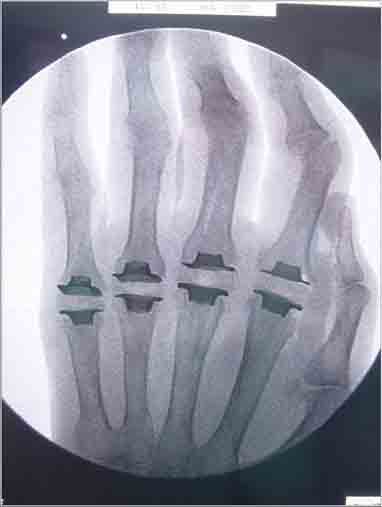

患者李阿姨,58歲,7年前診斷為“類風(fēng)濕性關(guān)節(jié)炎”,尤其是左手第2-5掌指關(guān)節(jié)腫脹壓痛,掌指關(guān)節(jié)及腕關(guān)節(jié)不能進(jìn)行主動(dòng)運(yùn)動(dòng)。

經(jīng)人介紹,李阿姨找到了省級(jí)知名骨科專家、邦爾骨科集團(tuán)首席專家、嘉興邦爾骨科醫(yī)院院長(zhǎng)趙凱教授,并進(jìn)行“人工指間關(guān)節(jié)置換術(shù)”。

術(shù)后患者恢復(fù)良好,關(guān)節(jié)活動(dòng)度恢復(fù)正常。

術(shù)前關(guān)節(jié)畸形

術(shù)后假體位置良好